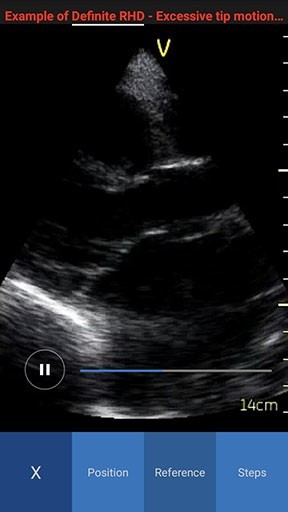

- Reference - Provides access to multiple ultrasound image examples for normal view and a few common pathologies for the current scan plane. You can access all available reference images swiping left or right.

NOTE: By default the reference image tab is activated when you press the info icon for the first time. The white color in the image header represents an example of a normal image, while red color represents an example of a pathology image.

Reference Image Pathology